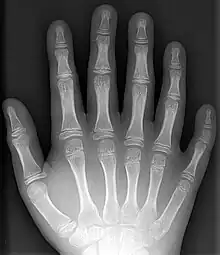

- Polydactyly – additional fingers or toes[6]